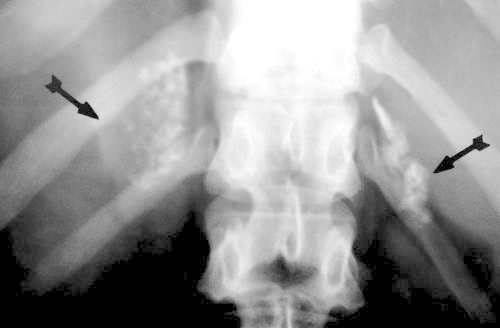

This coned down plain film of the abdomen details bilateral adrenal calcification. Note that in this instance, the right adrenal gland is slightly higher than the left. Courtesy of: Ashley Davidoff, M.D. |

The most common cause of adrenal calcification is hemorrhage occurring in the perinatal period or as a result of trauma. Other less common entities producing calcifications in the adrenal include:

Uncommon causes include:

The idiopathic causes have no known etiology. |